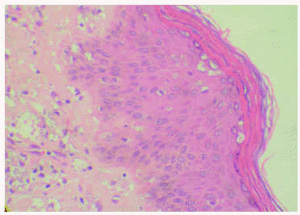

La biopsia cutánea mostró una epidermis con hiperqueratosis homogénea sin paraqueratosis y mínimo infiltrado inflamatorio. Se observaban múltiples amastigotes en el interior de los queratinocitos, con degeneración vacuolar y libres a todos los niveles de la epidermis, incluyendo la capa granulosa y entre la queratina de la capa córnea. También se observaron en menor proporción en el conducto excretor ecrino y en el acrosiringio. En la dermis y la hipodermis se apreciaban múltiples organismos intra y extracelulares, entre los haces de colágena, alrededor de las glándulas ecrinas, entre los adipocitos y alrededor de los vasos sanguíneos (figs. 2 y 3).

Fig. 2.--Numerosas leishmanias a todos los niveles de la epidermis, incluida la granulosa y entre la queratina de la capa cornea. (Hematoxilina-eosina, x400.)